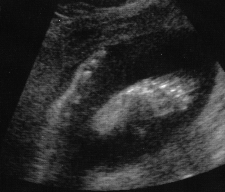

Pregnancy at 28 Weeks

First facial view.